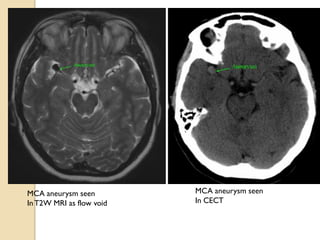

MCA aneurysm seen

InT2W MRI as flow void

In CECT

MCA aneurysm seen InT2WMRI as flow void MCA aneurysm seen In CECT